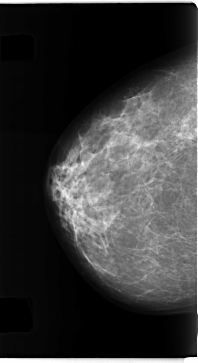

C_0271_1.RIGHT_MLO

RIGHT_CC LINES 4712 PIXELS_PER_LINE 2568 BITS_PER_PIXEL 12 RESOLUTION 50 NON_OVERLAY